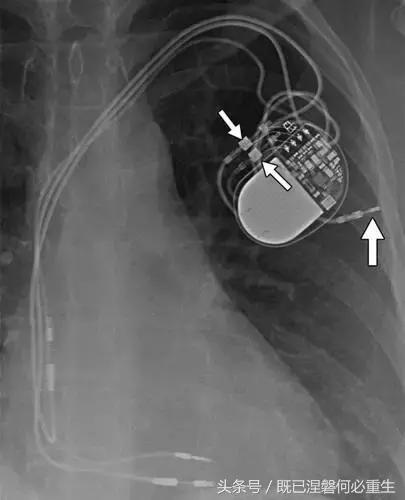

图。 9发生器引线断开。 移出的装置的放射线照片显示从末端完全退出的电极的外观(箭头)。 少数发电机没有容易识别的标志; 因此,制造商不能确定。

图10一名40岁女子的遗弃电极。 Medtronic发生器有两个端口(小箭头),但存在三个导联(一个心房和两个心室)。 针对传统的起搏器,有效导线的数量将等于或小于端口数量。 相针对端口的外部引线指示一个或多个引线被放弃。 因此,将端口数量与引线数量进行比较通常有助于识别丢弃的引线。 两个右心室导联之一以前发生故障,被放弃,而不是电极提取程序的风险并发症。 废弃的电极封盖(大箭头),以防止电气干扰。 未使用的端子也加盖并堵塞。